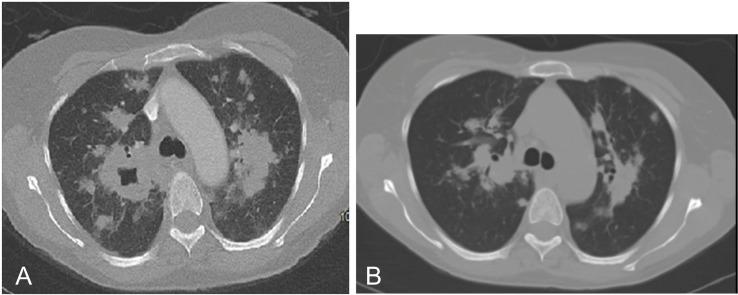

We report a rare case of a patient with Janus kinase 2-positive myelofibrosis on ruxolitinib, presenting with indolent pneumonia and cavitary lung lesions. Initial transthoracic biopsy was non-specific, but thoracoscopic biopsy revealed necrotising granulomatous disease caused by pneumonia (PJP). The patient, initially treated with trimethoprim-sulfamethoxazole, was switched to atovaquone due to gastrointestinal intolerance. Given the patient's immunosuppression and extensive cavitary lesions, an extended course of atovaquone was administered, guided by serial imaging, resulting in clinical and radiological improvement. Unfortunately, the patient later passed away from a severe SARS-CoV-2 infection before complete radiographic resolution was observed. This case highlights the importance of recognising atypical PJP presentations causing granulomatous disease in immunosuppressed patients. While rare, documenting such cases may improve diagnosis using less invasive methods and help determine optimal treatment durations for resolution of these atypical infections.

我们报告了一例接受鲁索替尼治疗的 Janus 激酶 2 阳性骨髓纤维化患者,表现为惰性肺炎和空洞性肺病变。初始经胸活检无特异性,但胸腔镜活检显示由肺炎(PCP)引起的坏死性肉芽肿性疾病。由于胃肠道不耐受,患者最初接受甲氧苄啶-磺胺甲噁唑治疗,随后改为阿托伐醌。鉴于患者免疫抑制和广泛的空洞性病变,根据连续影像学检查结果,给予阿托伐醌延长疗程,从而改善了临床和影像学结果。不幸的是,患者后来因严重的 SARS-CoV-2 感染而去世,在此之前尚未完全观察到放射学缓解。本病例强调了识别导致免疫抑制患者发生肉芽肿性疾病的非典型 PCP 表现的重要性。虽然罕见,但记录此类病例可能有助于使用侵入性较小的方法进行诊断,并有助于确定这些非典型感染的最佳治疗持续时间以达到缓解。